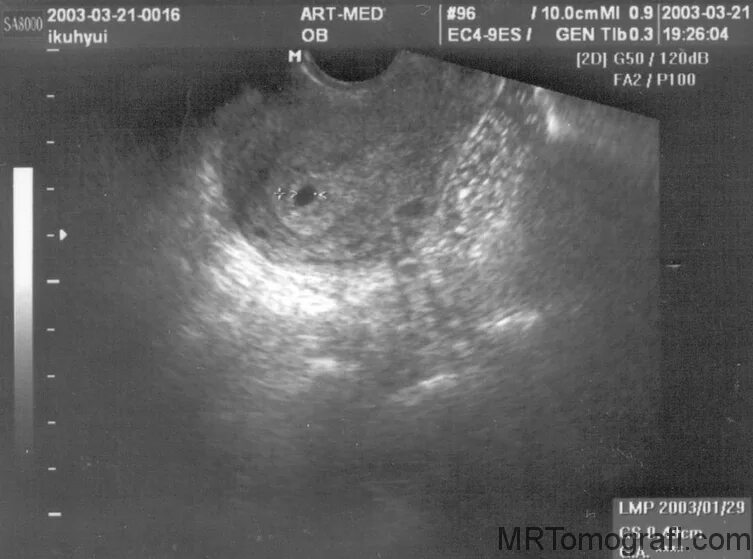

На узи можно определить раннюю беременность